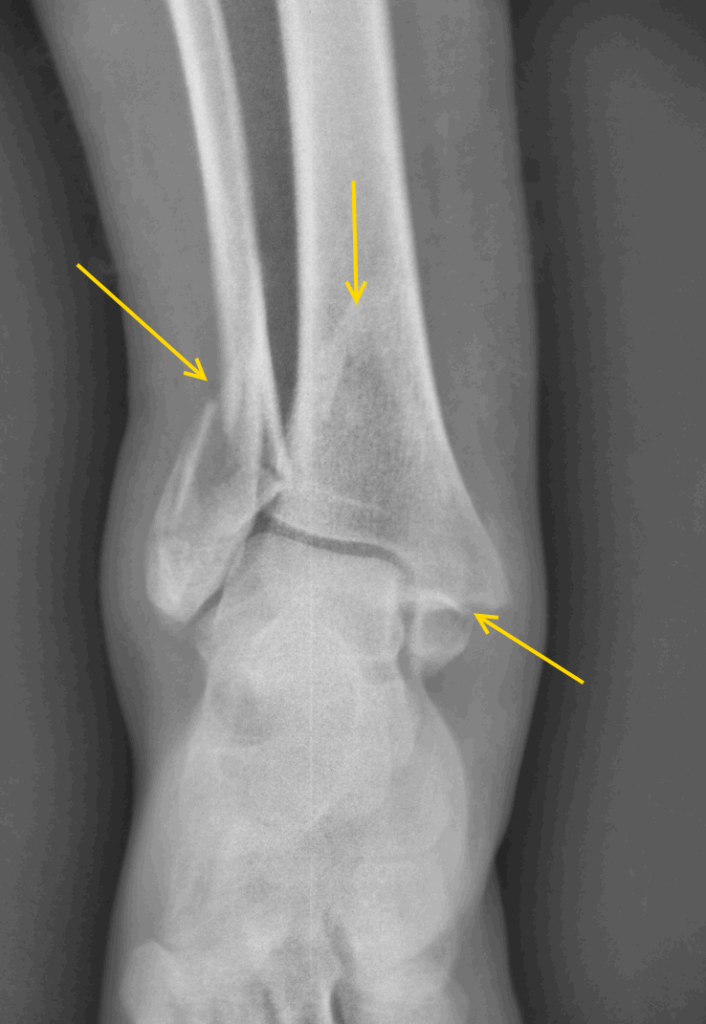

Достаточно рентгенологического сканирования, чтобы определить, почему болит голеностопный сустав в случае его механического повреждения. Более информативную картину дают прочие методы инструментальной диагностики:

Перелом – это достаточно распространенный вид травмы голеностопного сустава, на долю которого приходится около 15% от общего числа механических повреждений костно-суставных сегментов опорно-двигательного аппарата. Происходит опосредованное воздействие травмирующей силы, то есть при жестком фиксировании задней части стопы ее передний отдел продолжает движение. Травма (перелом) голеностопа возможна при падении с высоты, в результате неудачного приземления при выполнении физических упражнений, катании на лыжах, коньках. При получении травмы дальнейшее перемещение или движение человека становится весьма ограничено, так как голеностопный сустав болит. Что делать?

Не следует производить пораженной нижней конечностью какие-либо физические действия. Человеку нужна помощь медицинского работника и абсолютный покой, так как характер повреждения можно определить лишь при рентгенологическом исследовании. Нужно немедленно доставить пациента в ближайшее медицинское учреждение или вызвать Скорую помощь.